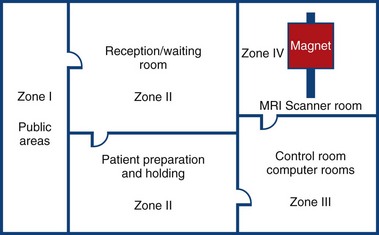

MRI Zone 4

Zone 4: Magnet Room

Authorised access only

The scan room door is always locked when unattended

Metal is removed

Danger signs

When the scan room door is opened, the MRI Safety barrier must be implemented at all times by MRI personnel

Forms for safety and consent

MRI Zone 3

Zone 3: Control Room

All metal removed

Locks on doors

Caution signs

Authorised access only

MRI Zone 2

Zone 2: Patient Screening and Prep

Patients and families undergo screening and are cleared to enter the magnetic area

MRI Zone 1

Zone 1: Unrestricted area (public walkway)